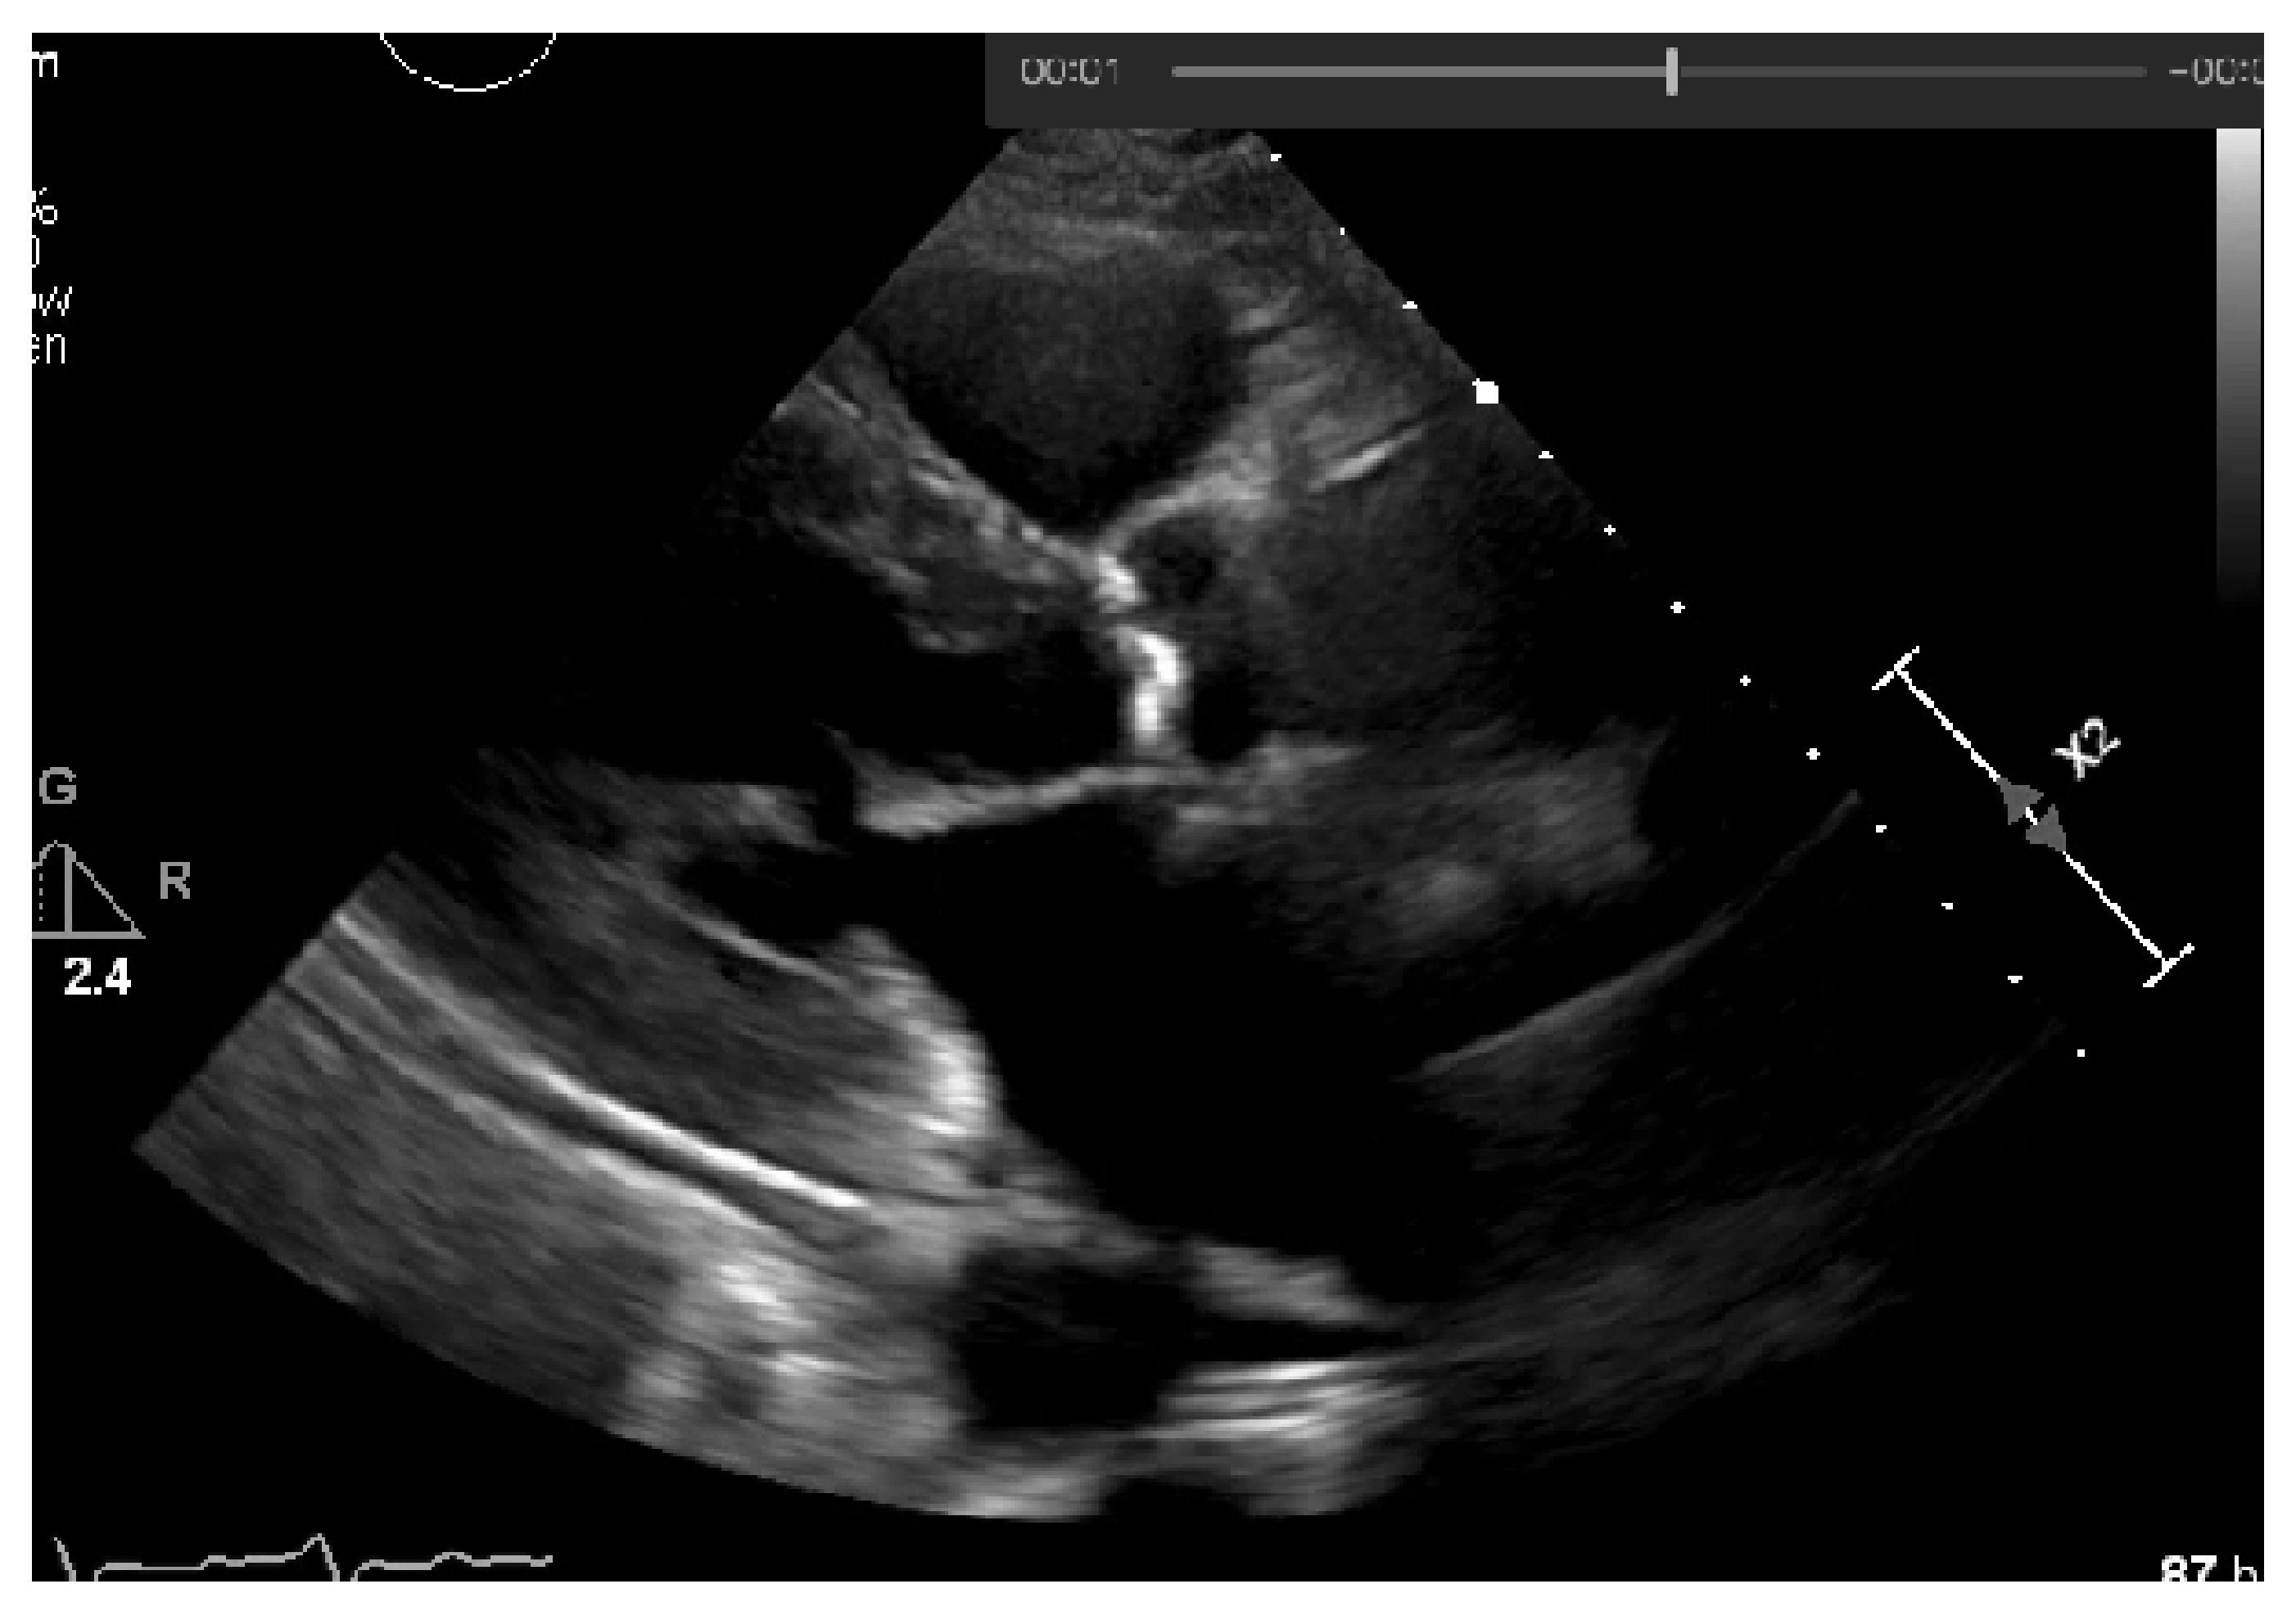

Achieving a dynamic threshold will normalize our echocardiography images, allowing our model to identify the calcium in different cases with different gains. The calcium presence can be seen in Figure 18 and is marked by a red circle.

Figure 18. Calcium in the binarized image.